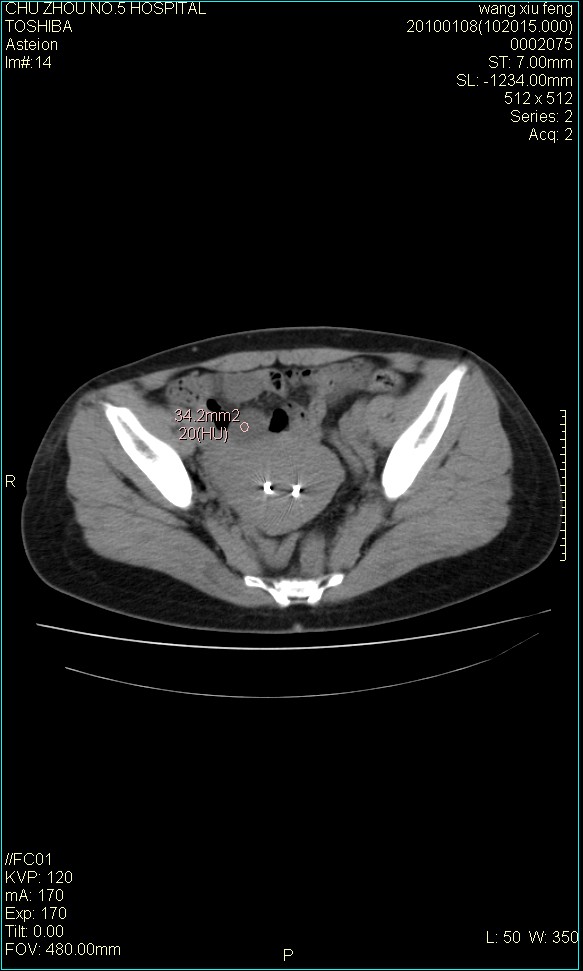

f-41,左乳腺ca术后4年,b超示:子宫右上方囊性包块约5.5*3.4cm,前日行胸部ct平扫未见明显异常。

考虑右侧卵巢囊腺瘤?

右侧卵巢囊肿或小囊腺瘤。

考虑肠系膜囊肿可能性大

考虑右侧卵巢囊腺瘤?建议增强!

考虑右侧卵巢囊腺瘤。

考虑右侧卵巢囊性占位性病变(囊肿?囊腺瘤?)。